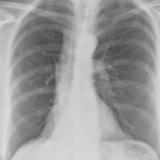

Gallery Lobar Collapse

Lobar Collapse

LUL Collapse

Album: LUL Collapse